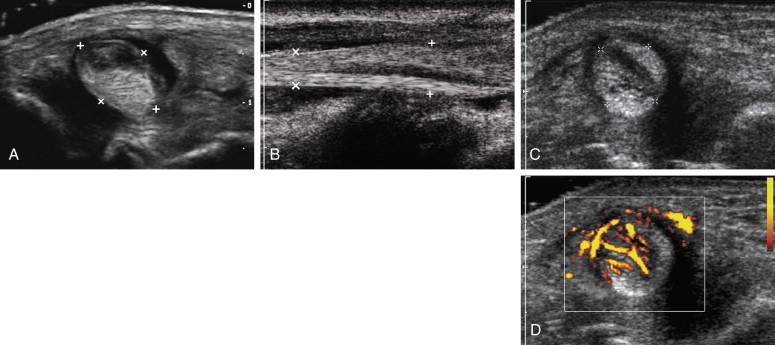

Neoplasms of the tendons are extremely rare, but giant cell tumors (GCTs) of the tendon sheath are the second most common cause of a mass in the hand. They are benign lesions that are histologically identical to pigmented villonodular synovitis. They are typically slow growing and painless and occur along the volar surface of the fingers. GCTs are solid, homogeneous, hypoechoic masses that are adjacent to the tendons and often partially surround the tendon ( Fig. 11-7 ). High-frequency color Doppler will generally show readily detectable internal blood flow and the lesions may be quite vascular. Because they arise from the sheath and not the tendon, they do not move with the tendon when the finger is flexed and extended ( e-Fig. 11-4 and ).

F igure 11-7, Giant cell tumors in different patients. A, Longitudinal view of the interphalangeal joint (arrow) of the fourth finger shows a solid, hypoechoic mass (cursors) adjacent to the distal aspect of the flexor tendon (asterisk) . B, Transverse view of the fourth finger shows a hypoechoic mass (cursors) that partially encases the flexor tendon (asterisk) . Transverse gray-scale (C) and power Doppler (D) views of the thumb show a solid, hypoechoic mass that completely encases the flexor tendon (asterisk) .